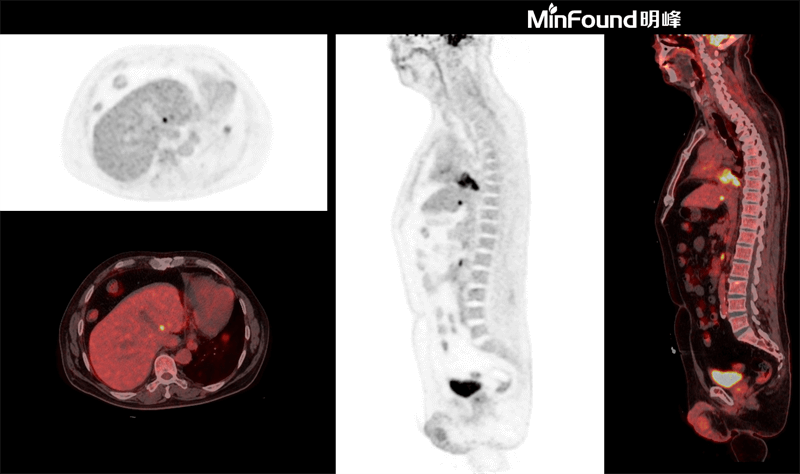

ScintCare PET/CT 730T

ScintCare PET/CT 730T employs a 4th-generation PET detector where lutetium-yttrium oxyorthosilicate (LYSO) crystals are individually coupled to SiPM detectors without the optical conductor (1: 1 coupling and 100% coverage). The digital SiPM detector considerably minimizes photon loss, resulting in improved time resolution (380 ps), system sensitivity (23.5 cps / kBq), and image uniformity, ultimately resulting in high-resolution images under well-curated radiation dose control.

ScintCare PET/CT 730T axial FOV reaches 40.3 cm width, enabling the whole-organ scan just by one-bed position and the whole-body scan by two-bed positions in about 3 minutes time. The ultra-fast data acquisition greatly supports the large patient throughput.

Respiratory gated PET/CTaims to eliminate the effects of motion artefact and provide a more accurate interpretation of pulmonary nodules and lymphadenopathy.

MinFound's digital gating technology is implemented directly, and can be set in the exam application. This technology not only saves additional preparation time, but also reduces overall examination duration.